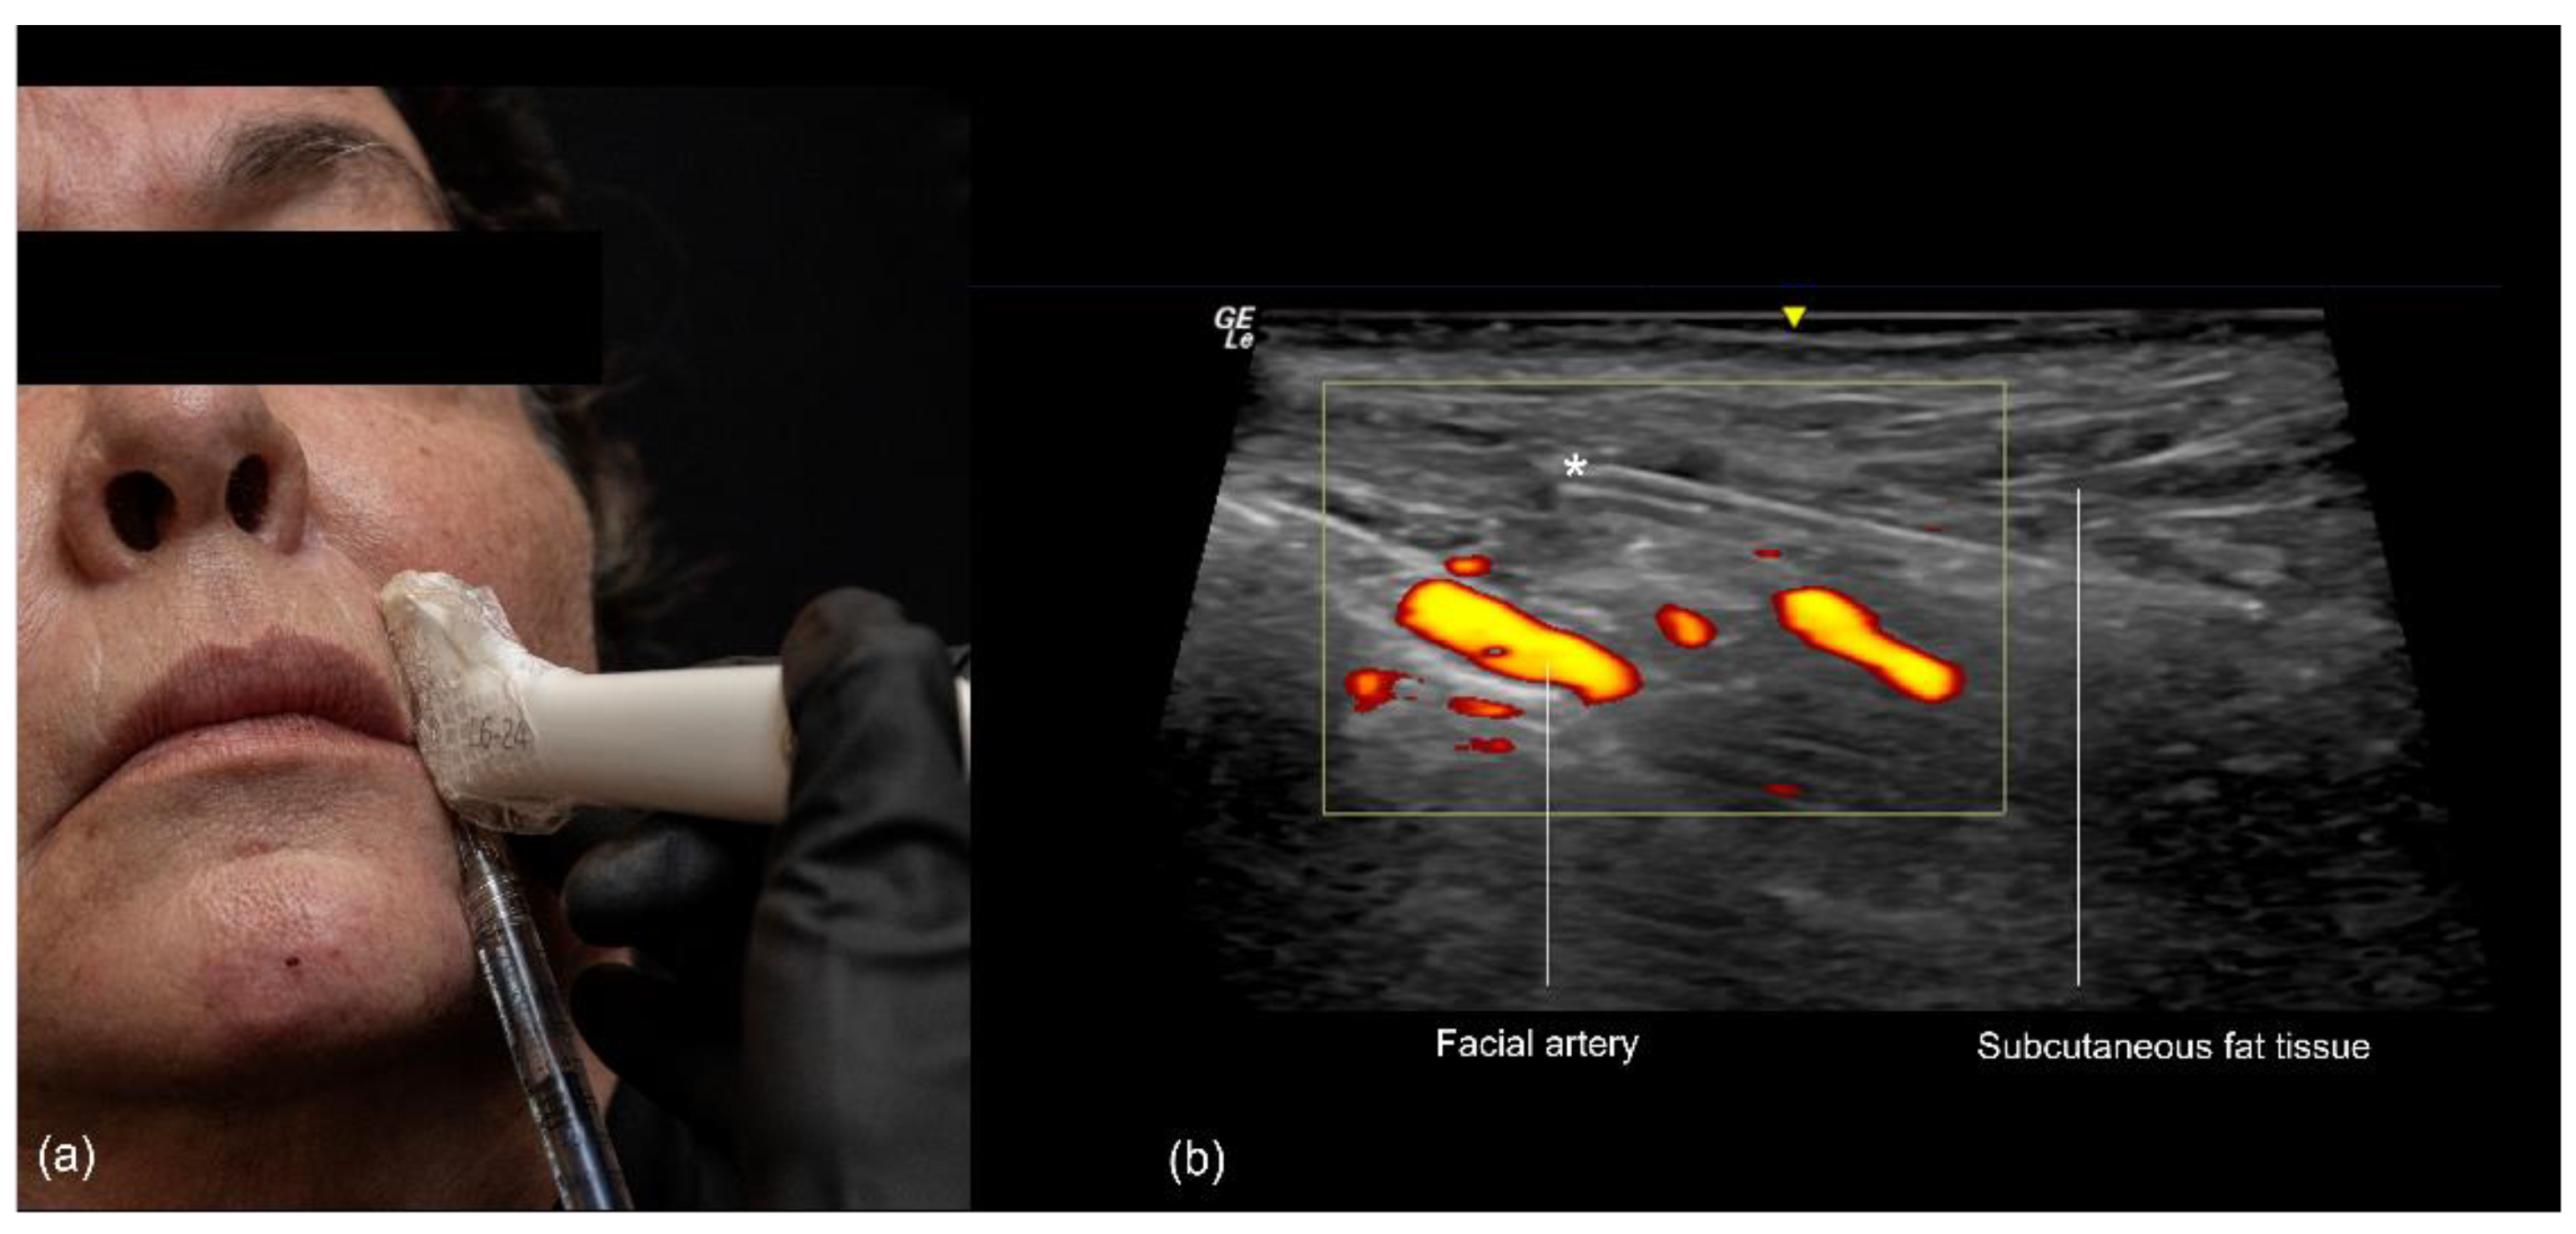

The procedure begins with the insertion of the cannula into the skin and subcutaneous tissue. The entry point is typically located 1 to 1.5 cm lateral to the oral commissure, following the natural wrinkle line. A 25 G or larger blunt-tip cannula is used. The ultrasound probe is then positioned along the cannula’s trajectory (in-plane technique), with a small amount of sterile gel applied for conductivity (Figure 10). The operator confirms that the cannula is correctly positioned within the desired layer, ensuring that its tip is not in contact with any branches of the facial artery or vein. Once the correct position is verified, the filler is slowly injected retrogradely, under ultrasound guidance, from the nasal to the labial angle.

Figure 10.

US-guided injection in the nasolabial fold (a) In-plane technique, scan while injecting. (b) Color Doppler US imaging showing the cannula in the subcutaneous fat tissue at 18 MHz, and its tip (*) outside of vessels.